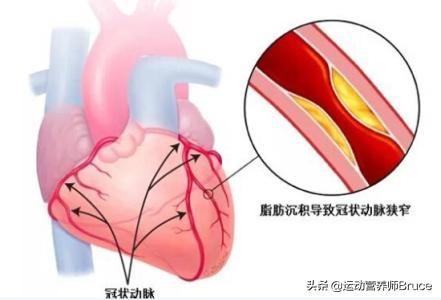

血管狭窄を引き起こし、最も深刻なプラークは、心血管プラーク、または頸動脈プラークであり、これらのプラークの悪化は、心筋虚血、脳虚血につながる;積極的に制御しない場合、あるいはプラークの血栓症の破裂が発生し、心筋梗塞、脳梗塞をもたらす。

頸動脈プラークが50%未満でLDLが高くない場合は、投薬しなくても一時的に観察することができる。頸動脈クラス狭窄が50%以上、またはプラークが柔らかい場合は、プラークをコントロールするためにスタチン投薬が必要である。心血管プラークも悪化を防ぐためにスタチンの服用が必要である。また、糖尿病、高血圧、高脂血症を積極的にコントロールする必要があり、LDLの目標値は理想的には2.6未満、あるいは1.8未満まで下げるとより安全である。

重要なのは特に冠動脈、頭頸部動脈に50%の動脈狭窄や不安定なプラーク形成がある動脈プラーク患者には、アスピリンと併用してスタチン療法を行うべきである。プラークを狭窄・安定化させるスタチンと、破裂した内皮での血栓症を予防するアスピリンの併用は、心血管イベントのリスクを有意に低下させるため、動脈プラークの治療と心血管・脳血管イベントの予防のための古典的な組み合わせであり、礎となる薬剤である。